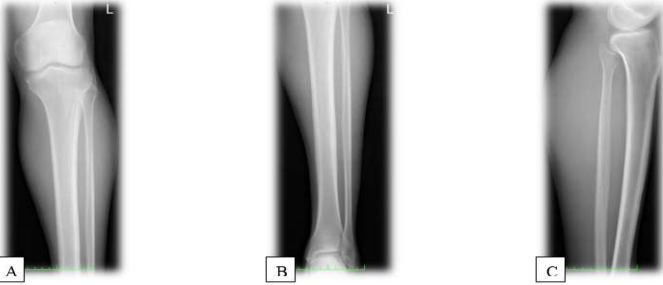

The following day, the patient underwent radiofrequency ablation (RFA) under CT guidance for osteoid osteomas in the left tibia, accompanied by a biopsy. The procedure was complicated by 2nd-degree burns at one of the ablation sites, which were later managed by plastic surgery. During the follow-up, wound cultures from the skin lesions tested positive for S. aureus. No other complications were encountered. Histopathology of the left tibial lesion biopsy revealed thickened trabeculae of bone with adjacent loose fibrovascular stroma and prominent osteoblastic rimming, which was consistent with OO. Postoperative radiographs were taken, and they demonstreated no abnormalities (Figure 7). During the follow-up examination, another bone scan (Figure 8) was performed after the operation. A tiny focal area of abnormal tracer uptake was observed involving the frontal bone along the lateral aspect of the right orbit, which is suggestive of a frontal bone osteoid osteoma.

Figure 7: Postoperative X-rays. (A) AP X-ray of the left tibia showing resolution of the cortical sclerosis and periosteal reaction at the midshaft region. (B) AP X-ray of the left tibia demonstrating normal bony architecture with no signs of the previous osteoid osteoma. (C) Lateral X-ray of the left tibia showing the absence of the previously noted cortical lesions and confirming successful treatment with no recurrence.